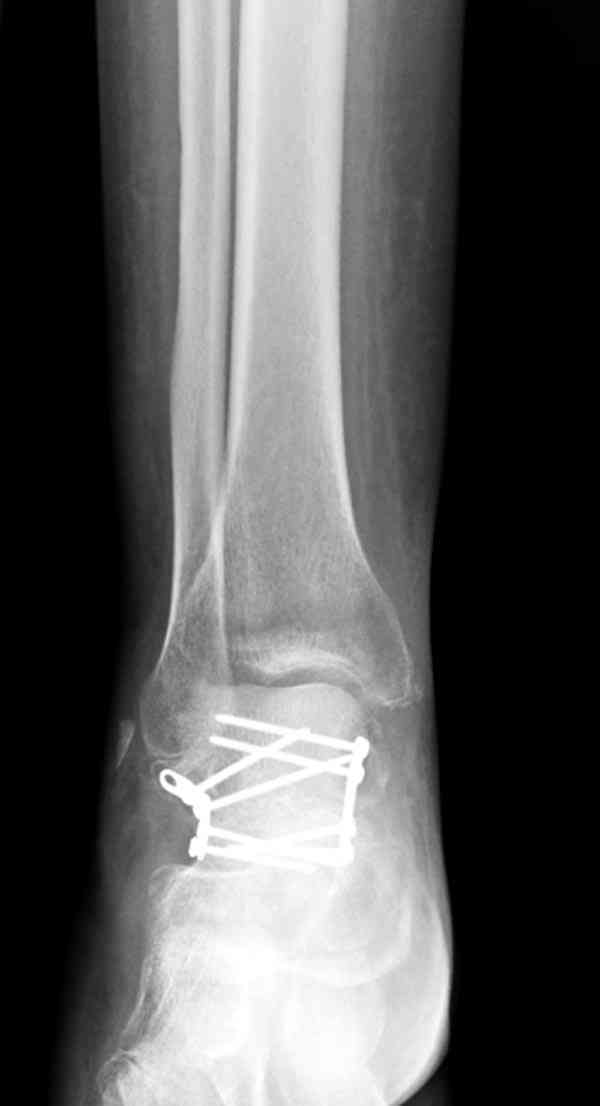

Случай с множественным оскольчатым переломом тарана оперированный из двойного доступа.

Через 14 мес.: